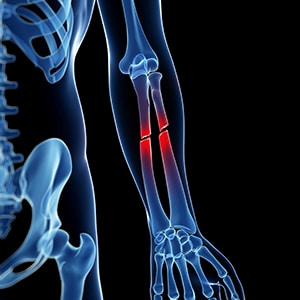

Traumatic Fracture

Trauma and Fractures | OASIS Orthopaedics Melbourne Traumatic Injury & Fracture Treatment - My Toronto Physio Traumatic Spine Fracture - Goodman Campbell All Types of Fractures & Trauma - Dr. Prajaktam Lende's Niva Ortho Care | Orthopedic Surgeon In Nagpur | Orthopedic Doctor in Nagpur | Traumatic Fracture